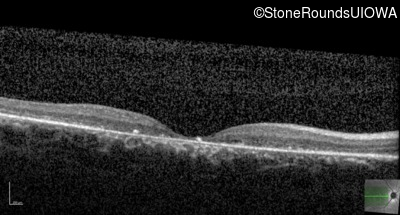

Optical Coherence Tomography - Right - 10/160 -1 sc

Exemplar / OCT Stack